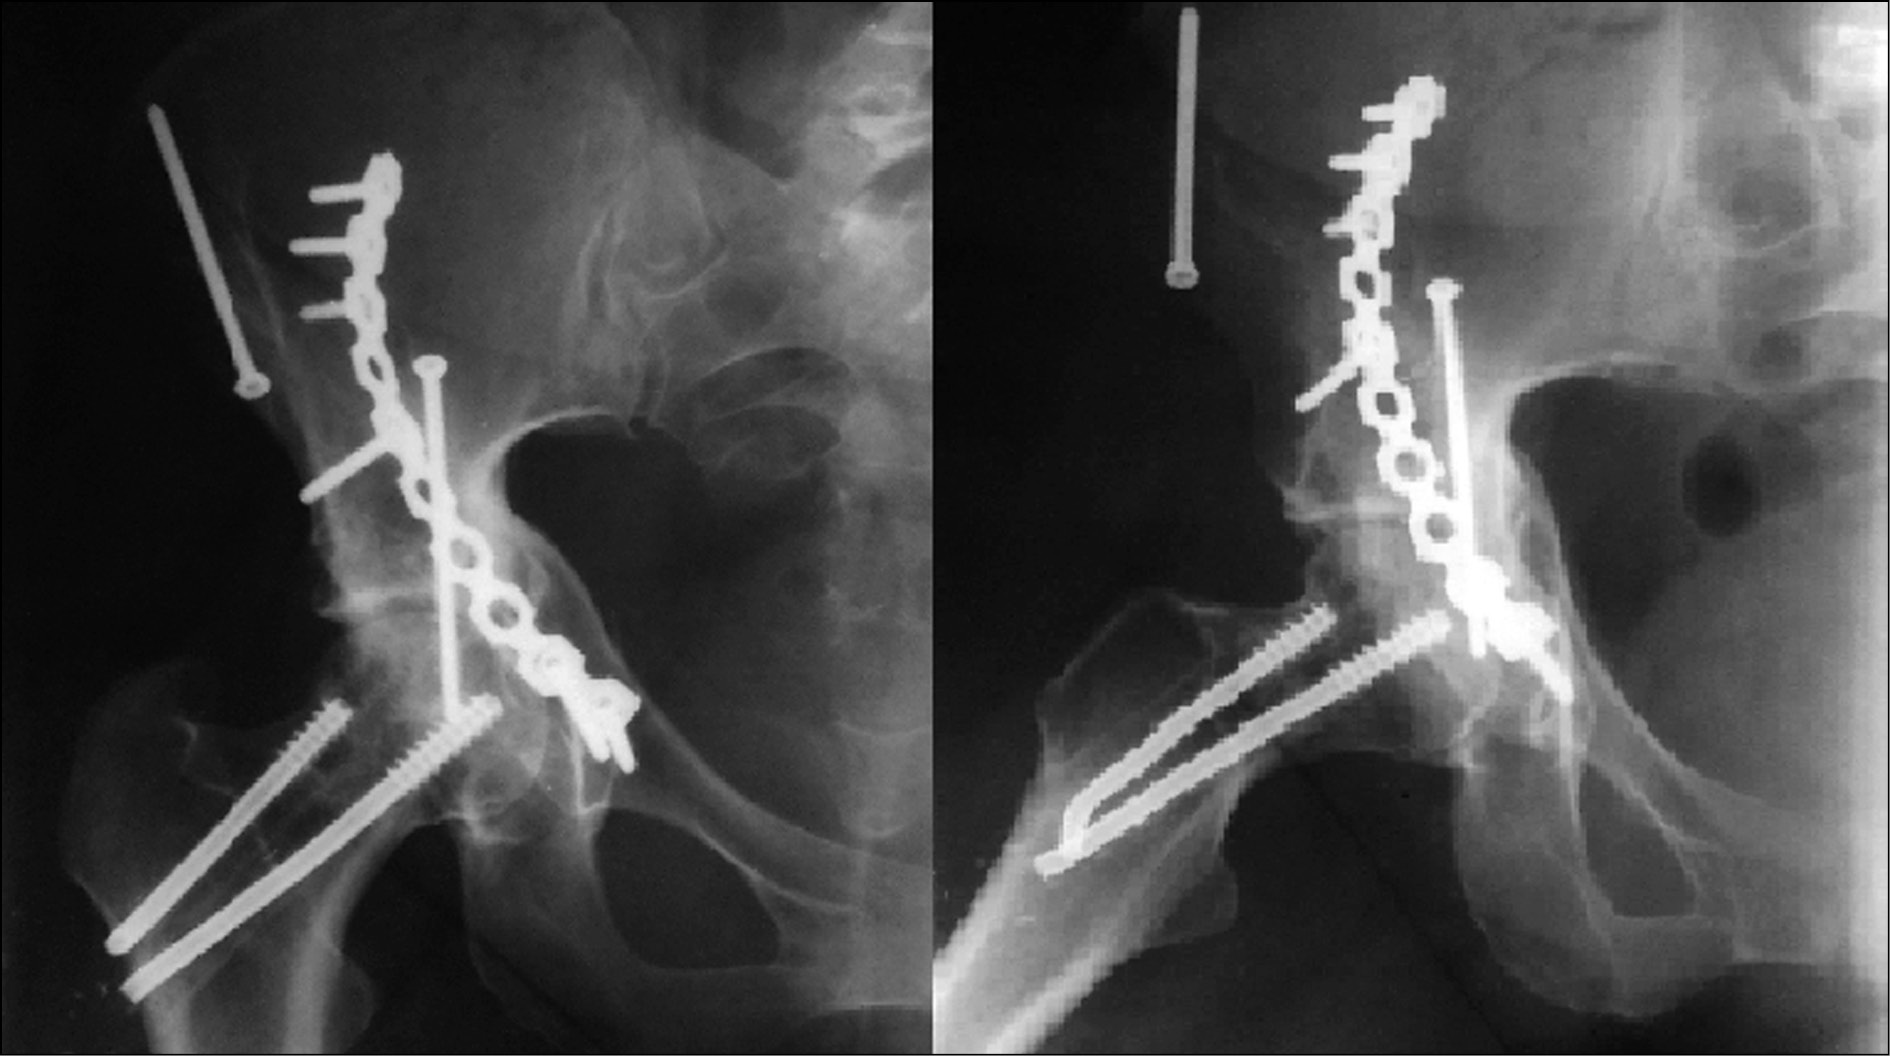

На 11-е сутки после поступления пациентке выполнены операции: перкутанный остеосинтез шейки правого бедрам тремя канюлированными винтами с биологически активным кальций-фосфатным покрытием (патент РФ № 81427) и остеосинтез переломов правой вертлужной впадины подвздошно-паховым доступом пластиной с биологически активным кальций-фосфатным покрытием (патент РФ № 113945) (рис. 2).

Рис. 2. Контрольные рентгенограммы пациентки Б.: прямая проекция (а), запирательная проекция (b), подвздошная проекция (c)

Послеоперационный период протекал без особенностей. Раны зажили первичным натяжением, швы сняты на 12-е сутки. После выписки пациентка наблюдалась в динамике. Переломы вертлужной впадины и шейки бедра консолидированы. Рентгенологическое подтверждение консолидации получено через 4 мес.